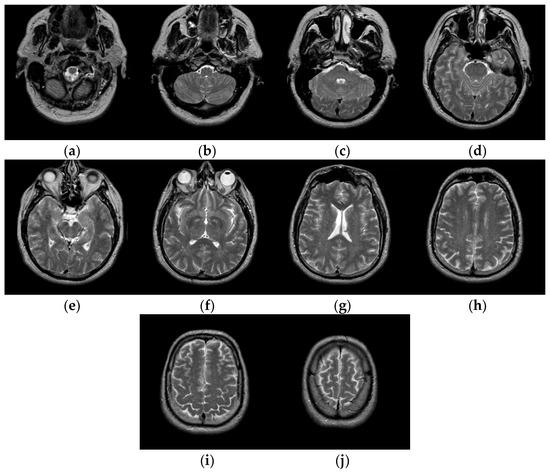

The test images we used in the experiments are from “The Whole Brain Atlas” of Harvard Medical School Image Library (http://www.med.harvard.edu/aanlib/home.html (accessed on 20 September 2021)). Due to limited space, we chose ten brain slices #022~#112 to demonstrate the performance of our proposed algorithm. These ten brain slices are shown in Figure 7. All the experiments in this paper are run on Intel(R) Core (TM) i7-7700HQ CPU @ 2.80 GHz 2.80 GHz, 16 GB RAM, windows 10 and programming language is Python3.6. The parameter settings of the proposed algorithm and the number of thresholds are shown in Table 1.

Figure 7.

Ten brain slices (a) slice #022, (b) slice #032, (c) slice #042, (d) slice #052, (e) slice #062, (f) slice #072, (g) slice #082, (h) slice #092, (i) slice #102, (j) slice #112.